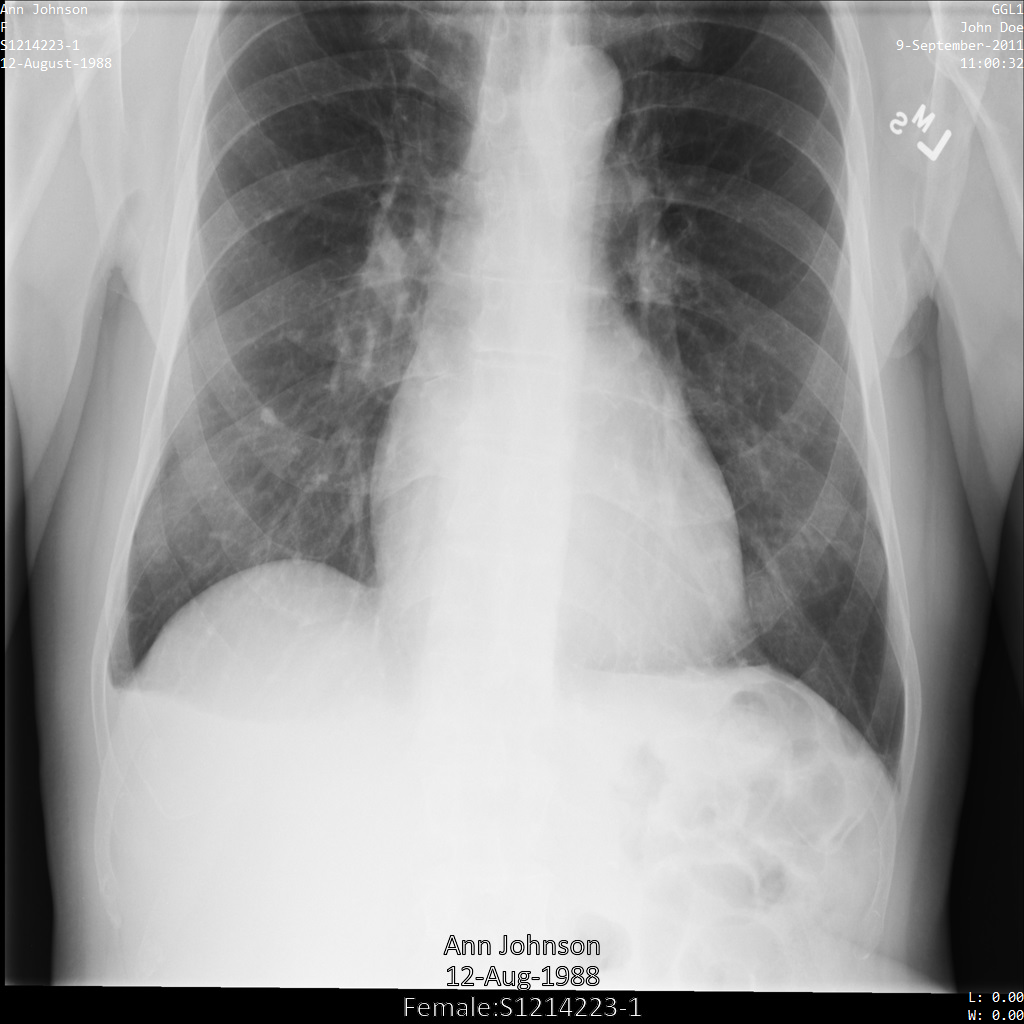

Imagem de exemplo

Alguns exemplos nesta página contêm uma saída da imagem desidentificada. Cada exemplo usa a seguinte imagem original como entrada. Pode comparar a imagem de saída de cada operação de desidentificação com esta imagem original para ver os efeitos da operação: